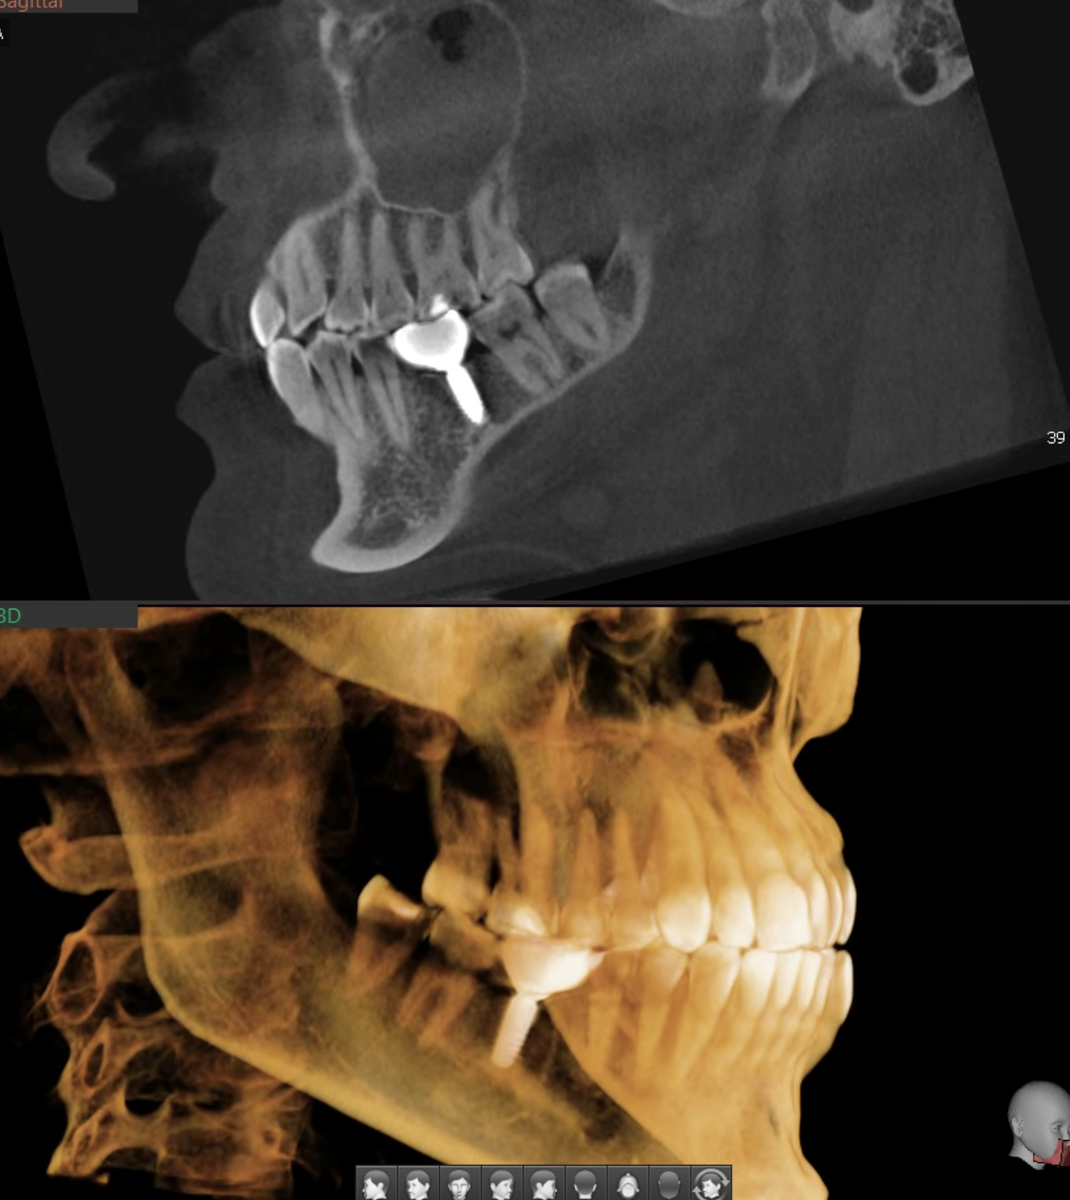

В конце 2024 года ко мне, как к пародонтологу, на консультацию пришла пациентка. Жалобы классические - дёсны "уползают" куда-то с опасной скоростью, корни зубов оголяются. Страшно. Кажется, что ещё немного - зубы посыпятся изо рта.

Посмотрим на срезы КТ:

Затем рассматриваю ситуацию во рту - только комплексно можно оценить реальную картину и правильно интерпретировать состояние. Что вижу - признаков хронического воспаления тканей пародонта нет:

• дёсны бледно-розовые, плотные;

• кровоточивости нет;

• межзубные сосочки на месте;

• нет деструкции кости, костные перегородки сохранны, костные карманы не определяются.

Это не пародонтит. Это перегрузочный тип рецессий - невоспалительный. А прикус у пациентки весьма интересный.